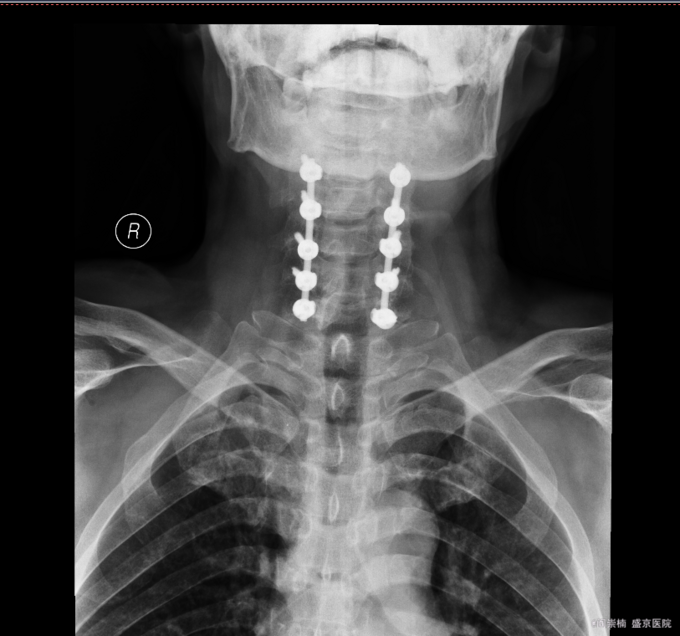

患者入院后完善相关检查,明确诊断,手术指征明确,于2015-11-17日于全麻下行颈椎后路单开门椎板减压,侧块螺钉内固定术,术后经抗炎、止疼等对症治疗后,患者恢复顺利,切口愈合良好,今日可出院。